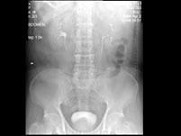

- 多项选择题男,67岁, 无痛性血尿1月,IVP和MRI检查如图示, 下列说法正确的是 ( )

A、IVP示左侧中组肾盏未见显影